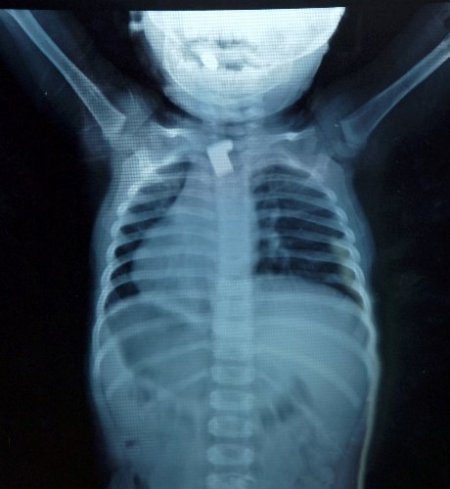

Kardeşinin haber vermesiyle durumdan haberdar olan aile, çocuğu hemen Elbistan Devlet Hastanesi Ana Çocuk Sağlığı Merkezi’ne getirdi. Hastanenin Çocuk Hastalıkları Uzmanı Opr. Dr. Ünal Adıgüzel, küçük çocuğun filminin çekilmesini istedi. Çekilen filmde çocuğun boğazında anahtar parçası olduğu görüldü. Yapılan tahlillerin ardından çocuk ameliyata alındı. Yaklaşık 20 dakika süren bir operasyonda özel aletler marifetiyle anahtar parçası çıkarıldı. Hastanede kontrol altında tutulan Üzeyir Balıkçı, öğle saatlerinde taburcu edildi.

Opr. Dr. Ünal Adıgüzel, “Hastamız 1,5 yaşında. Kırık bir anahtar parçasını, anahtarın uç kısmını yutma şikayetiyle müracaat etti. Çektiğimiz filmde anahtar parçasının yemek borusuna takılı olduğunu tespit ettik. Operasyonla yemek borusundan çıkarttık.” dedi.